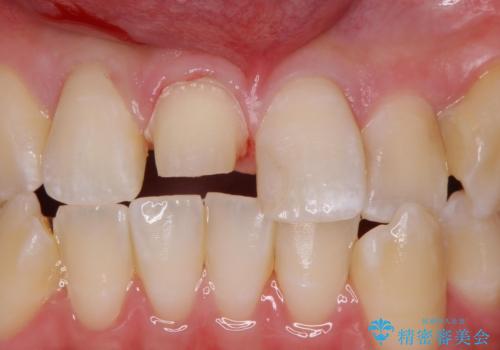

前歯の色が気になる。オールセラミッククラウンでのやり替え

- 前歯のかぶせ物の色が気になるとのことで来院された患者様です。

セラミッククラウンで作り変えていきます。

色・形ともに改善され、大変喜んでいただけました。